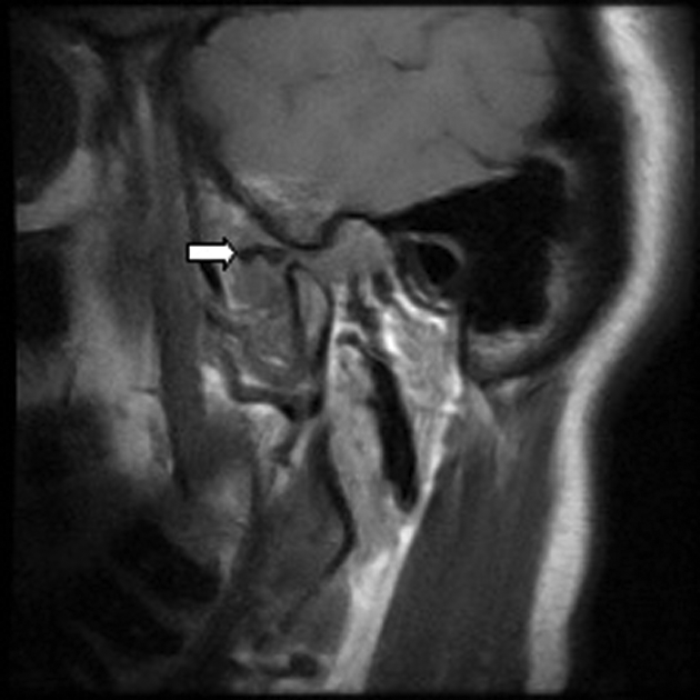

Figure 1: Innervation of the tympanic membrane. Figure 2: Sagittal T1W MRI of the left TMJ in the open mouth position showing an anteriorly displaced meniscus (white arrow). The meniscus should be positioned between the condyle and articular eminence.

A 45-year-old female presented with a three month history of left otalgia. Otoscopy was normal. On examination there was a palpable click of her left TMJ on opening, with deviation of the mandible to the right. The clinical findings suggested that the patient had internal derangement of the left TMJ (Figure 2).

Figure 2: Sagittal T1W MRI of the left TMJ in the open mouth position showing an anteriorly displaced

meniscus (white arrow). The meniscus should be positioned between the condyle and articular eminence.

Of patients with TMJ disorders, 70-78% present with otalgia. Magnetic resonance imaging (MRI) is the preferred imaging technique for the TMJs, being performed with the mouth open and closed in order to assess meniscal displacement and recapture.